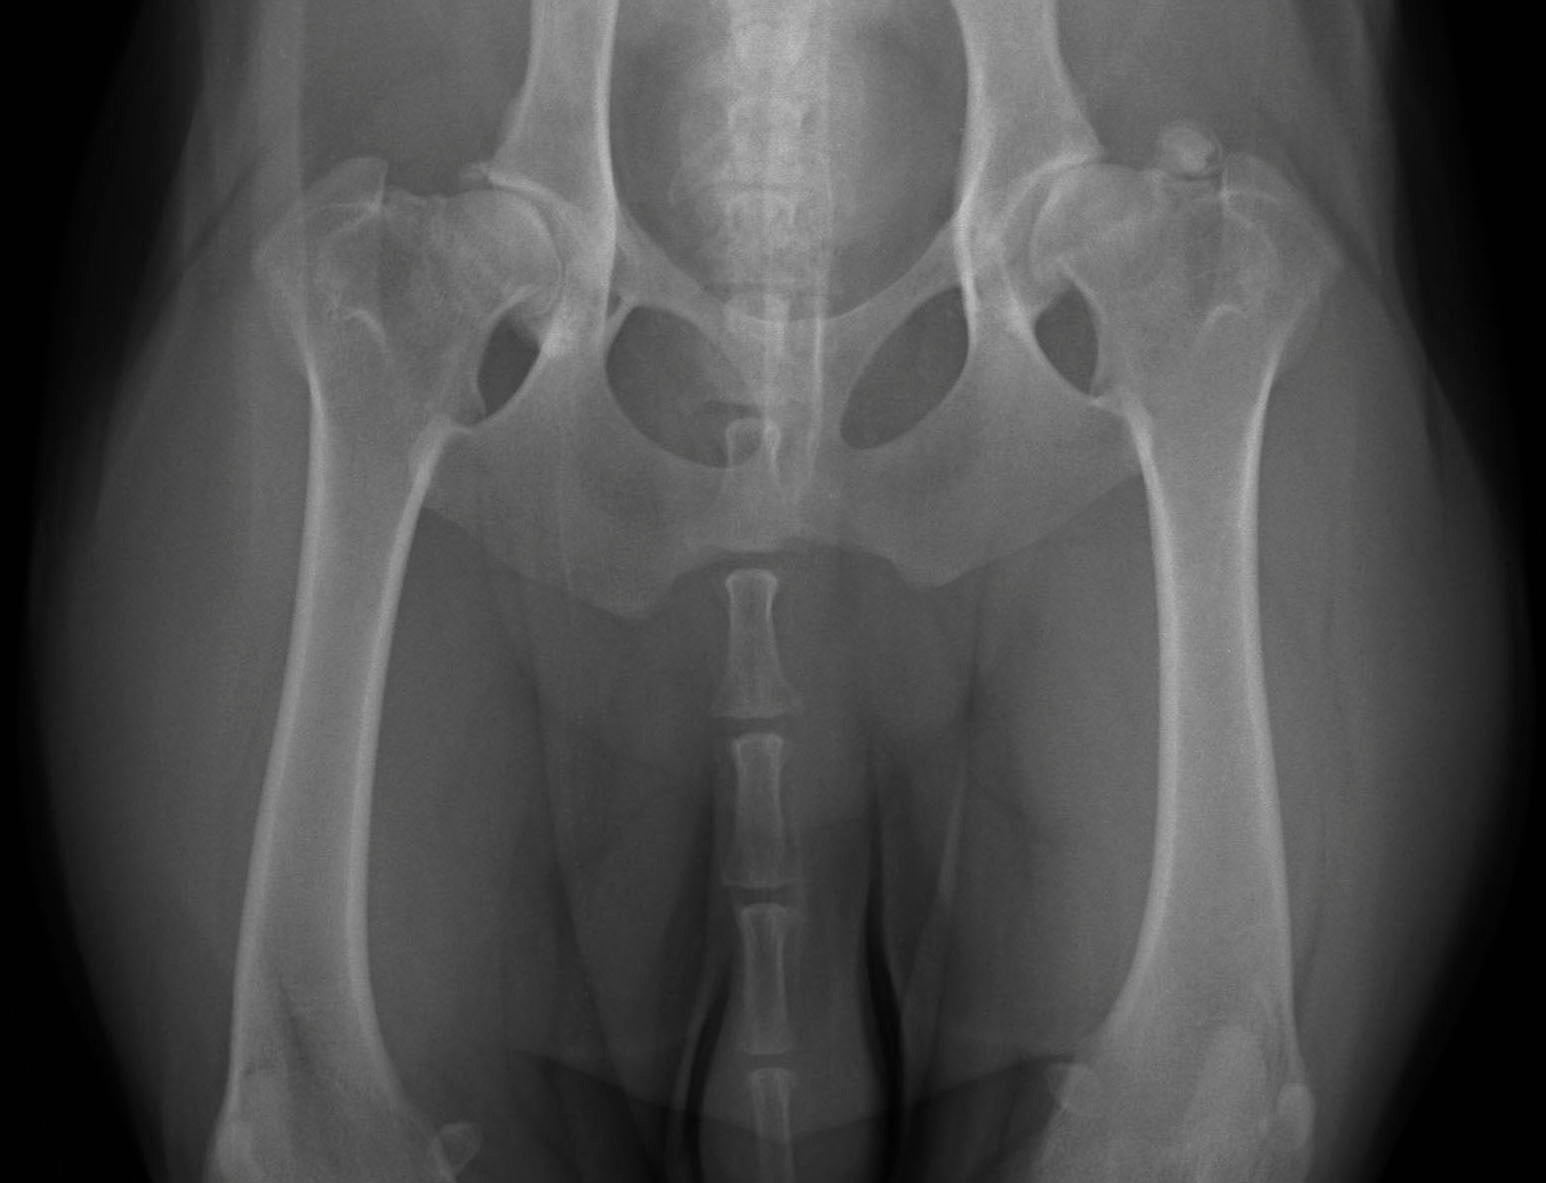

Hip pain can be very debilitating for dogs, especially in their senior years. And as a dog owner, you want to do everything you can to keep your dog happy, healthy, and pain-free throughout their lifetime.

The 3 Best Ways to Treat Hip Dysplasia in Dogs (CHD)

Treating Canine Hip Dysplasia found out your dear doggy has been diagnosed with Hip dysplasia.  You turn to the internet only to discover there is a lot of misinformation and not a lot of answers.